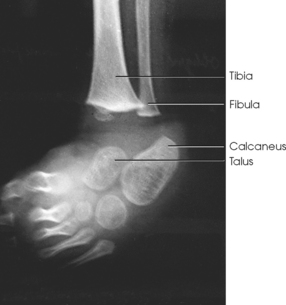

Structures shown: The image shows a true AP projection of the ankle joint, the distal ends of the tibia and fibula, and the proximal portion of the talus.

NOTE: The inferior tibiofibular articulation and the talofibular articulation are not “open” or shown in profile in the true AP projection. This is a positive sign for the radiologist because it indicates that the patient has no ruptured ligaments or other type of separations. For this reason, it is important that the position of the ankle be anatomically “true” for the AP projection shown (Fig. 6-92).